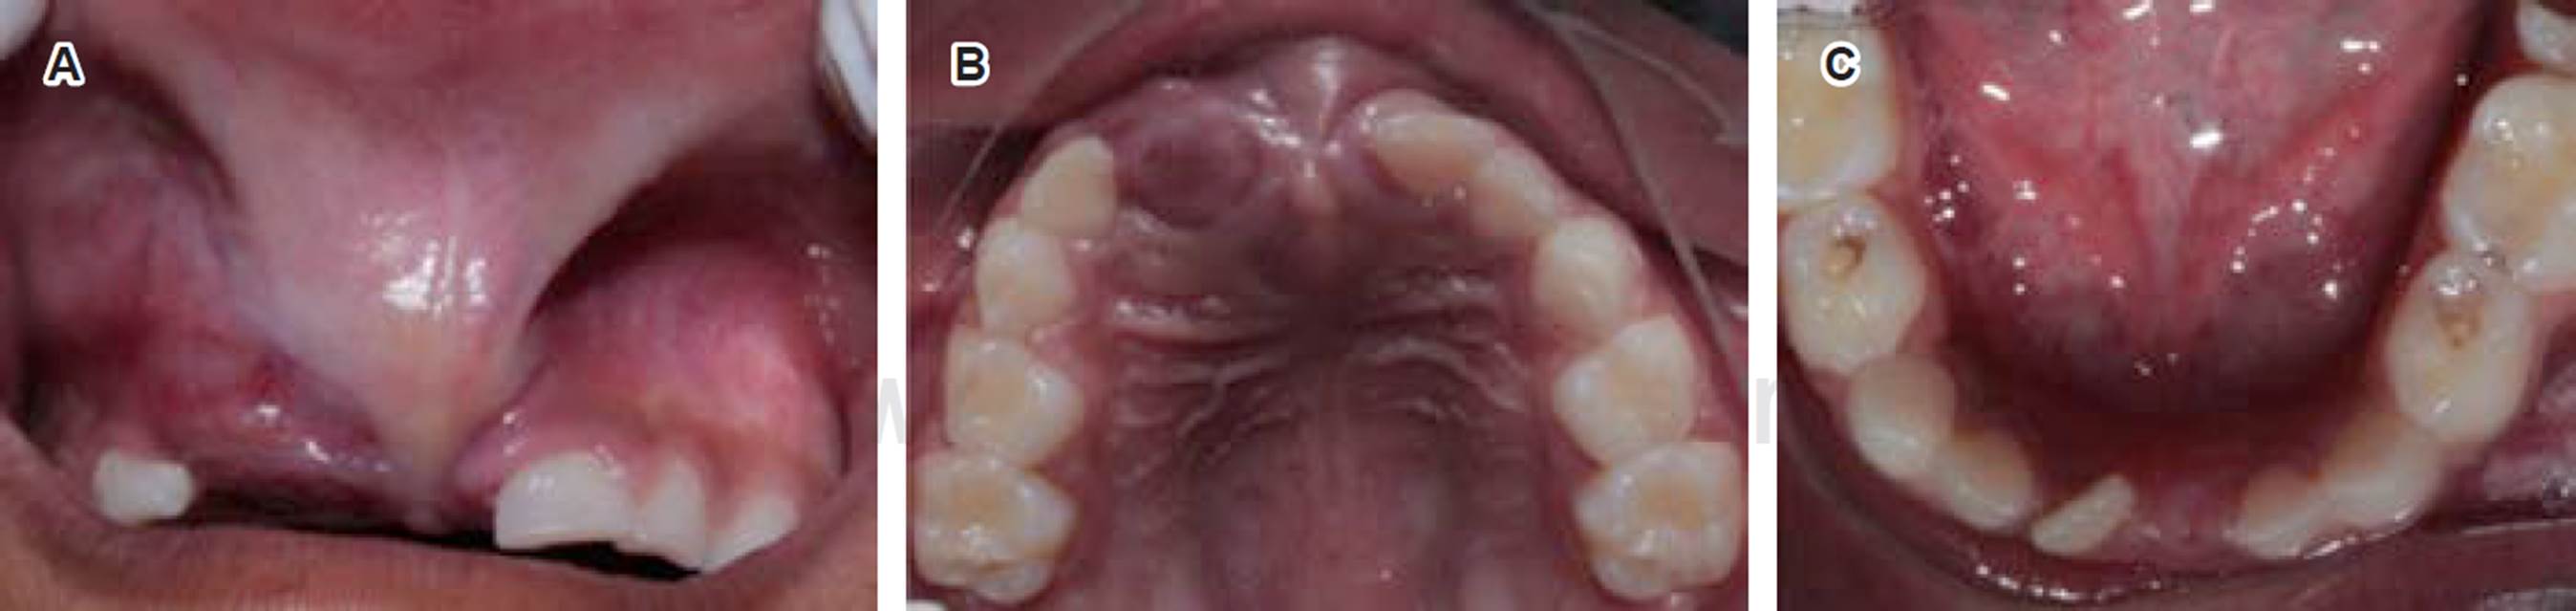

En el examen facial (Figura 1) se notó una clara asimetría y deformación moderada asociada al labio superior. Al examen intraoral, la mucosa labial superior mostró aumento de volumen por encima del frenillo labial, extendido hacia el canino superior derecho (Figura 2A) que involucra al reborde alveolar; se observó de igual manera en el paladar duro anterior, con un aspecto sésil y rojizo, con dolor a la palpación. Dentalmente, se encontraba la paciente en dentición mixta, la ausencia del OD 51 era por una extracción previa, el OD 61 mostraba desplazamiento distal (Figura 2B). Los OD 71 y 81 se habían exfoliado fisiológicamente y el OD 41 se encontraba en erupción temprana. En arcada inferior se observaron los órganos dentarios 72, 73, 74, 75, 41, 82, 83, 84 y 85, los molares deciduos inferiores presentaron lesiones por caries en esmalte y dentina, no hubo alteración en tejidos blandos en dicha arcada (Figura 2C); y en la arcada superior estuvieron presentes los OD 52, 53, 54, 55, 62, 63, 64 y 65.

Figura 2 Al examen intraoral es perceptible un aumento de volumen en la región anterior del maxilar (A), que va del paladar duro hacia la mucosa vestibular y frenillo labial superior, lo que ocasiona deformación del reborde alveolar (B). La encía inser tada con aspecto rojo-azulado. En los dientes de la arcada inferior se observan cavidades por caries en esmalte y dentina (C).